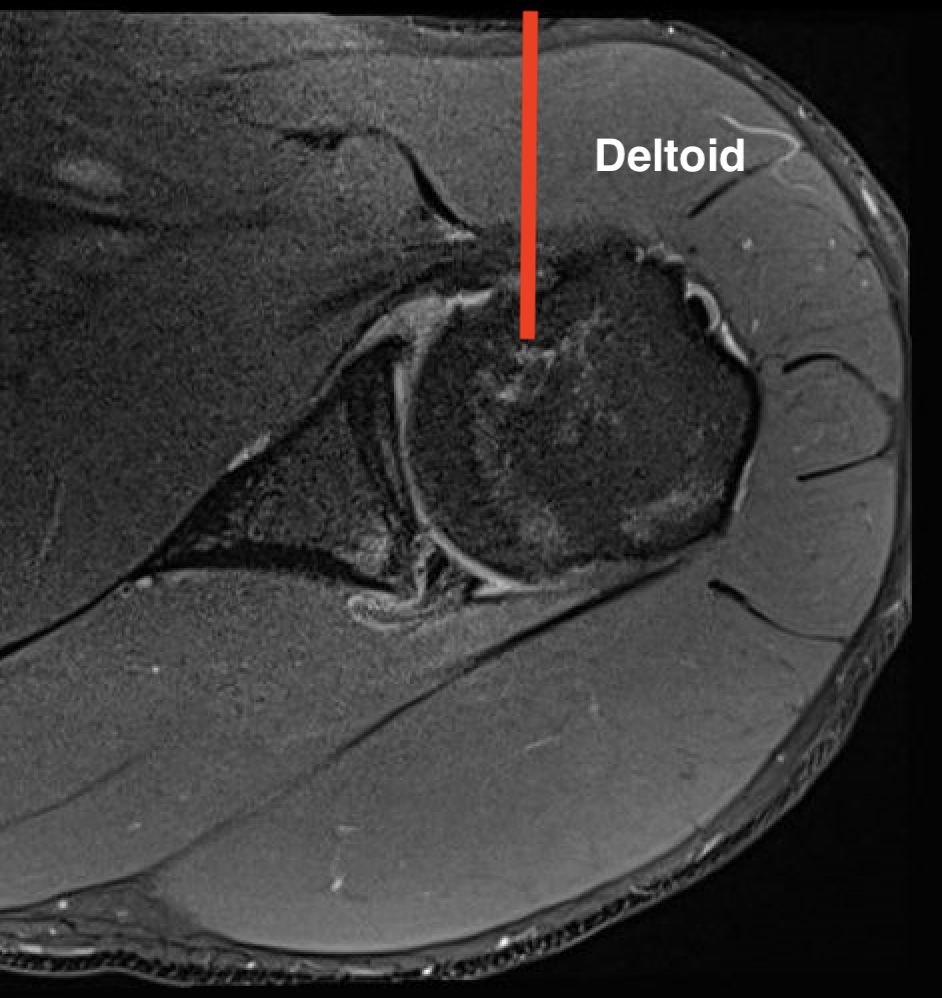

1.  Proximal humeral bony tumour

- direct lateral

- through deltoid muscle

- never deltopectoral (condemns patient to forequarter amputation)

Shoulder CSHumerus biopsy 1